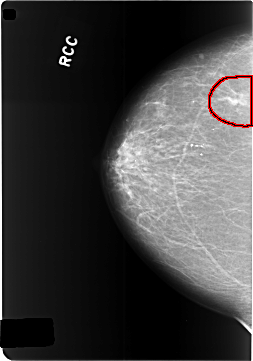

C_0340_1.RIGHT_CC

FILE: C_0340_1.RIGHT_CC.OVERLAY

TOTAL_ABNORMALITIES 1

ABNORMALITY 1

LESION_TYPE MASS SHAPE IRREGULAR MARGINS SPICULATED

ASSESSMENT 5

SUBTLETY 5

PATHOLOGY MALIGNANT

TOTAL_OUTLINES 1

BOUNDARY